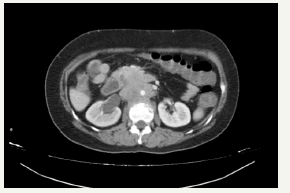

An upper endoscopy was performed and revealed the presence of a large amount of bilious content in the stomach and proximal duodenum. The third portion of the duodenum showed a proliferating violaceous mass, which was friable and completely obstructed the duodenal lumen (Figure 1). A CT scan evidenced a retroperitoneal mass infiltrating the duodenum, and was associated with dilatation of the proximal duodenum and stomach (Figure 2). An exploratory laparoscopy showed 8 x 8cm retroperitoneal mass involving the duodenum and para aortic lymph nodes. A palliative gastro jejunostomy bypass was performed. The pathologic study of the biopsies showed epithelial cells with corneal pearls and the immunehystochemistry study was positive for p63, confirming the diagnosis of squamous cell carcinoma of the cervix (Figure 3 & 4). Our patient improved with the above mentioned palliative bypass surgery

Figure 2:Abdomen and Pelvic CT Scan with contrast showing an infiltrating heterogeneous retroperitoneal lesion involving the duodenal second portion, causing dilatation of the proximal duodenum and stomach. Right sided hydronephrosis is also seen, caused by the retroperitoneal mass.